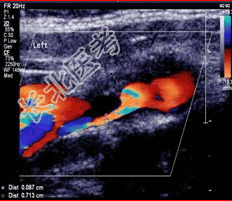

- [材料题] 患者男,59岁,因“右侧肢体麻木、无力,伴言语障碍及一过性意识丧失1个月”来诊。

- 简答题2、颅脑CT:未发现明显异常。颈动脉超声检查如下图。根据图像判断病变程度是什么?